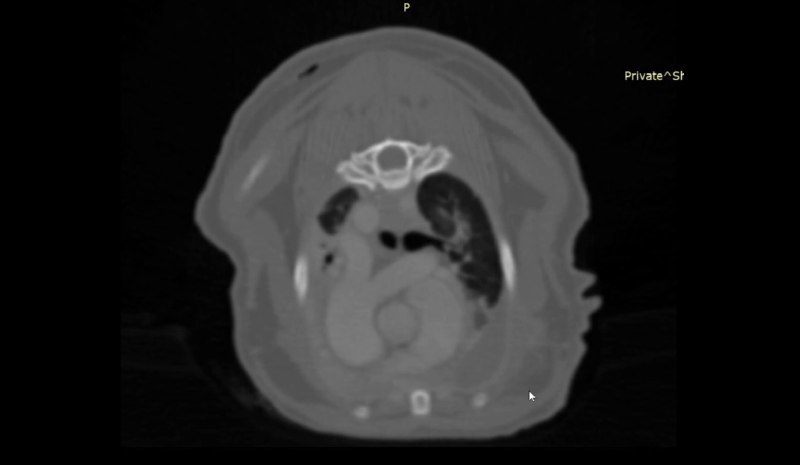

Компьютерная томография грудной клетки Описание:

• Плевральная полость: контуры париетальной плееры бугристые выражено утолщены и с гиперперфузией - паттерн «скомканного полотенца» наибольший объем которого характерно располагается вентрально каудально за сердцем (в области кардиодиафрагмального контакта); характерный паттерн пролиферации и его распределение для пиоторакса; двусторонний плевральный выпот в умеренном на момент исследования количеств.

о Полный компрессионный ателектаз КрЛеД с сохраненной перфузией и нормальными остроугольными краями

о Выраженные компрессионные уплотнения легочной паренхимы в вентральных сегментах всех прочих легочных долей ассоциированные с плевральным выпотом

о Сердце незначительно смещено дорсально за счет объема пролиферации мягкой ткани (фиброзная ткань наиболее вероятна)

о Стернальный лимфоузел: выраженное увеличение без четких контуров и область пролиферации мягкой ткани в их проекции, характерное для пиоторакса у кошек

1. KТ признаки пиоторакса в фиброзно-экссудативной стадии с выраженной фиброзной пролиферацией

2. Двусторонний плевральный выпот и компрессионные изменения легких

3. Признаков неопластического / метастатического роста не визуализируется

- Представленный паттерн пролиферации мягкой ткани париетальной плевры не является абсолютно патогномоничным, но в значительно большей степени характерен именно для фиброзной пролиферации, почти всегда формирующемся у кошек при пиотораксе. Окончательная (официальная) верификация возможна только по p-там гистологического исследования, но оно редко проводится у подобных пациентов.

- Кошкам с такими находками строго рекомендована установка двусторонних плевральных дренажей и стационарное печение